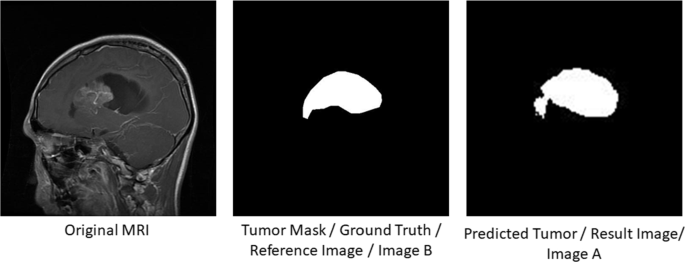

A brain tumor can form in the brain cells (as shown), or it can begin elsewhere and spread to the brain. As the tumor grows, it creates pressure on and changes the function of surrounding brain tissue, which causes signs and symptoms such as headaches, nausea and balance problems.